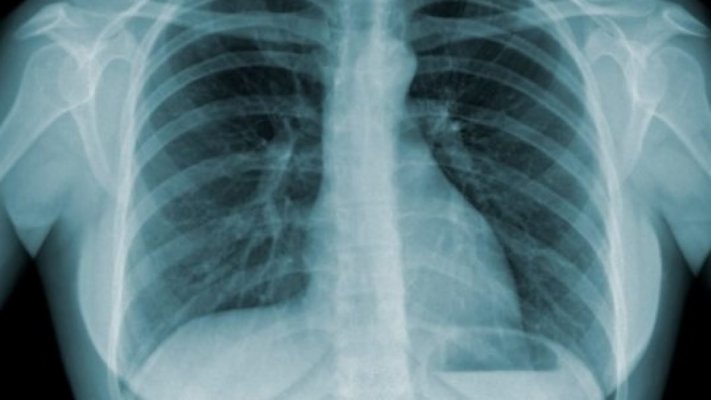

A autoridade de saúde explica que o rastreio começa por excluir doença ativa, através de sintomas e radiografia do tórax, e prossegue com um teste sanguíneo (IGRA) que avalia se houve contacto prévio com a bactéria.